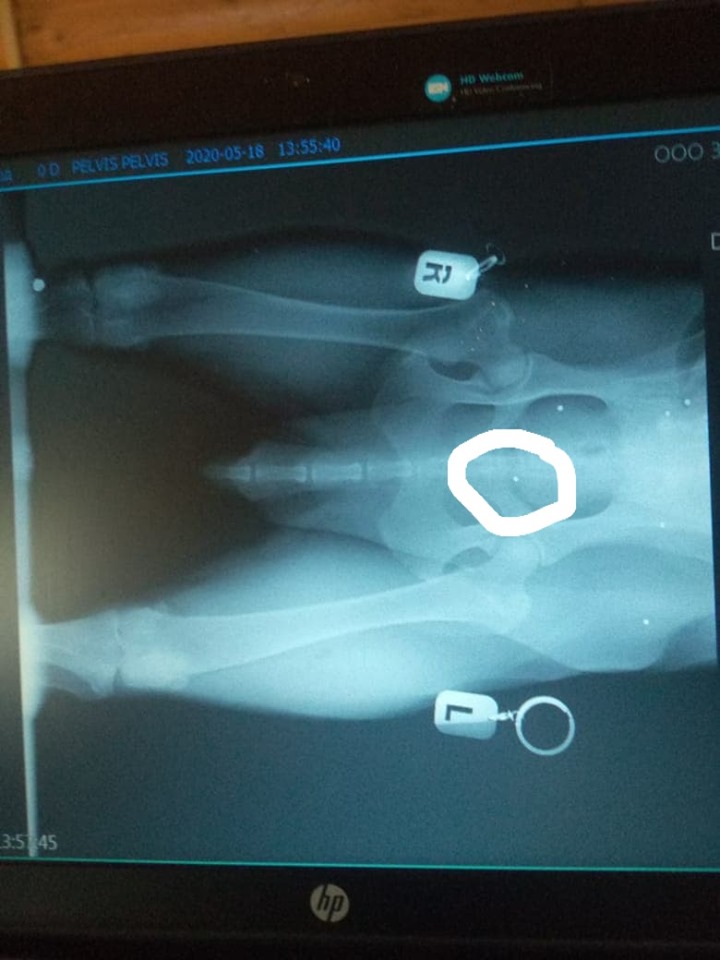

Рича кастрировали. Новообразование на семеннике отправили на гистологию. Кардиоисследование показало незначительные изменения, соответствующие возрасту и предыдущей жизни. Рентген ТБС показал наличие дроби в мягких тканях в районе ТБС и дробь в районе колена, которая как раз ему мешает, поэтому Ричард предпочитает не садиться, а лежать, стоять или ходить. Удалять дробь не советуют, так уже всё инкапсулировалось: операция по удалению опаснее, чем наличие дроби.

rentgen Rich.jpg

Рентген. Дробина, обведенная, а также в правом колене могут мешать ему

Тут их как минимум 6 или 7

Обведенная очень неудачно расположена. Ну и колено. Андрей Николаевич тоже на них обратил внимание.

При одной проекции трудно точно определить положение:(

Посмотрев и поняв что там 7 дробин, решили что мучать и крутить его бесполезно. Мешают две. Остальные вросли и на опорной двигательный аппарат - не влияют.